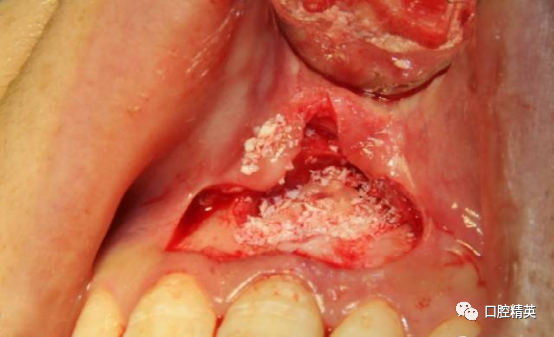

初步分离后可见较厚的囊壁暴露,夹持后分离囊壁与骨面,争取完整分离。

囊肿后壁与骨面粘连严重,术中破裂,可见大量豆渣样组织和药物颗粒。

初步清除。21根尖完全暴露。刮除21根尖区腭侧囊壁,此区域操作不便,易留有残留组织。